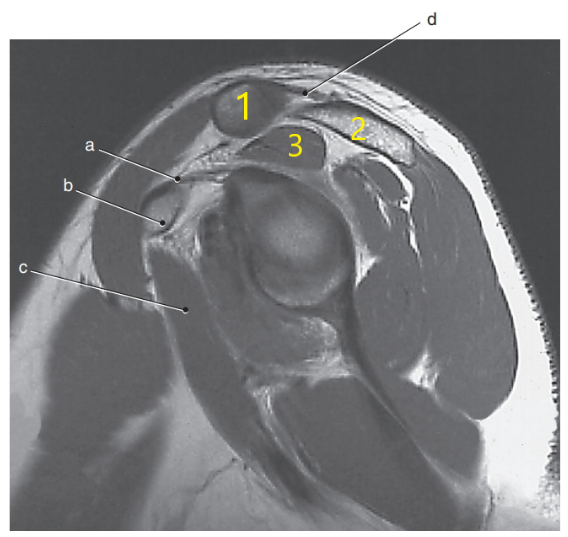

What is this special view of the shoulder joint called ?

Abduction external rotation

What is letter A pointing to ?

Supraspinatus muscle

What is letter c ?

Glenohumeral joint

What is # 2 ?

Lunate

Posterior glenoid labrum

What is letter d ?

Scapular spine

What is # 3 ?